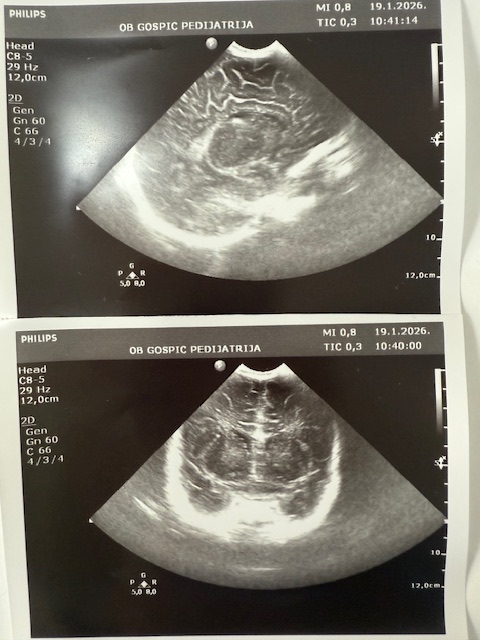

Objavljeno: 19/01/2026GOSPIĆ- Dječji odjel opće bolnice Gospić jedan je od manjih u Hrvatskoj, ali izuzetno aktivan. Uz redovnu djelatnost, ambulante, Dnevne bolnice i vođenja samog Odjela kao i Rodilišta što obavljaju tri liječnice specijalisti pedijatrije (Sandra Čubelić, dr.med., Linda Hibravi Kosić, dr.med. i Kristina Ilić, dr.med.), pri Odjelu radi i Ultrazvučna ambulanta u kojoj se već 20 godina jedini u Hrvatskoj radi dojenački probir na bolesti i razvojne poremećaje mozga i razvojni poremećaj zgloba kuka. Dakle naglašavamo da svako dojenče rođeno u Općoj bolnici Gospić obavi oba ova pregleda po principu “skrininga”, što znači da se traže poremećaji kod zdrave djece. Probir radi pedijatrica i ravnateljica bolnice, dr. Sandra Čubelić te smo analizom utvrdili da ovaj nadstandard koji imaju djeca Ličko-senjske županije godišnje se odradi kroz 1200 ultrazvučnih pregleda, odnosno tijekom ovih 20 godina učinjeno je oko 25 000 pregleda. U početku su se pregledi radili još u novorođenačkoj dobi, a sada je uobičajeno napraviti pregled dojenčadi u dobi od 1 mjesec. Svrha navedenog je otkriti poremećaj prije nego što se kod djeteta pokažu simptomi i znakovi bolesti pa moramo istaknuti da je kod dvoje djece izvedena operacija mozga prije nego je dojenče imalo ikakve poremećaje u smislu smetnji psihomotornog razvoja dok različite manje razvojne poremećaje se nađe bitno češće. Što se tiče zgloba kuka, razvojni poremećaji se graduiraju pa se teži poremećaji kao što je luksacija i subluksacija nađu rjeđe, dok se poremećaji u smislu displazije nađu češće, a svrha ovih pregleda je da se izliječe prije prohodavanja djeteta jer poremećaji koji se uoče nakon što dijete prohoda se teže i dugotrajnije liječe, čak i operativno. Inače kroz Dječji odjel Opće bolnice Gospić godišnje se obradi i liječi oko